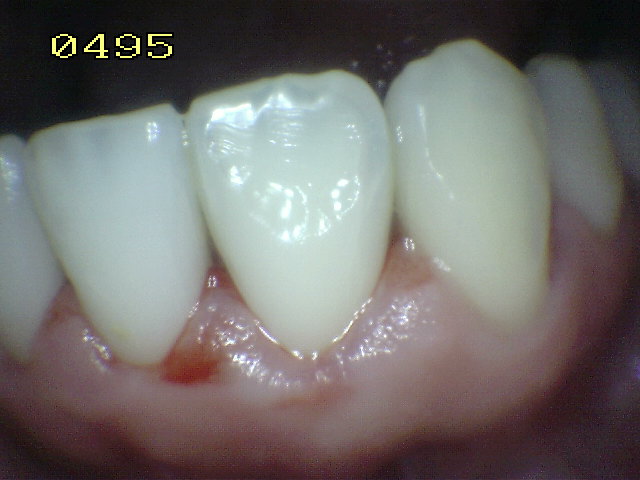

- Hacer examen visual de la superficie húmeda:

- Inicie desde el cuadrante superior derecho del

paciente

- Prosiga con la orientación de las manecillas del

reloj

- Inicialmente el examen visual se realiza con las

superficies húmedas.